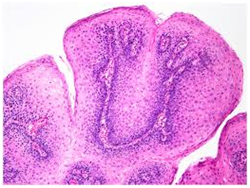

Histopathological statutes: The squamous epithelium displays finger like projections, the epithelial maturation pattern is orderly with epithelial hyperkeratosis. Spinous epithelial cells may depict cytoplasmic vacuolation with pale, clear perinuclear haloes, nuclear pyknosis and infrequent basilar hyperplasia. Oral squamous papillomas frequently display koilocytosis on account of the co-existent cytopathic influence. Atypical nuclear alterations may be exemplified; particularly with immune-compromised (HIV positive) individuals.9 The epithelium displays a typical maturation pattern with prominent hyperkeratosis. Epithelial to basal cell quantification is moderate (basilar hyperplasia) along with an extensive koilocytic transition.1 Virally induced carcinomas are the poorly differentiated, non-keratinizing tumours and may be enunciated in the tonsils of sexually active young men. Majority of the tumours elucidate the p16 proteins. Oro-pharyngeal cancers which are reactive for human papilloma virus (HPV) frequently depict basaloid morphology. Apart from a viral genesis, squamous papillomas may ensue from mechanical irritation or may be genetically determined as a constituent of Cowden’s syndrome.

Figure 2 Oral Squamous Papilloma with papillary projections

Figure 3 Papillomas with a fibro-vascular core.